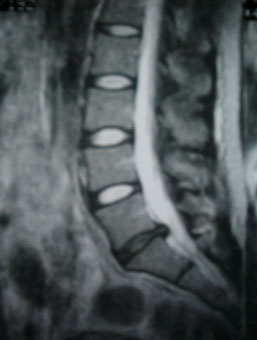

Cauda Equina Syndrome Secondary To Lumbar disc herniation ...

260 Adam, Hornea Cauda equina syndrome secondary to lumbar disc herniation B Figure 2 Preoperative MRI: axial section (A) and sagital ... Fetch Here